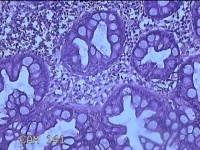

乙状结肠粘膜

性别

男

年龄

52岁

临床诊断

结肠息肉

一般病史

乙状结肠可见息肉

标本名称

大体所见

灰白粉红色组织小米大一团。

图3

自动采图系统很方便,图片采太多没病变的图,几张就够了,而且制片技术急需改进,

有点增生性息肉的感觉